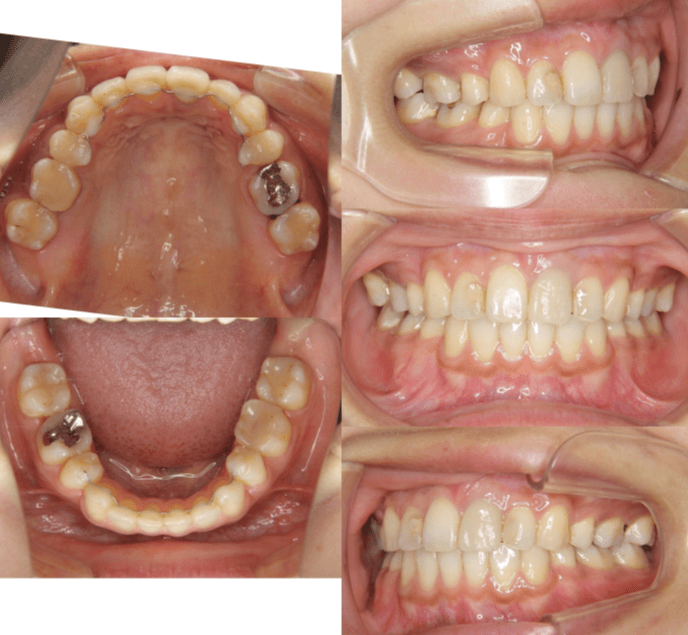

| 年齢・性別 | 30歳女性 |

|---|---|

| 主訴 | 歯並びの乱れ(叢生)を気にされて来院された。咬み合わせや審美的な改善を希望されていました。 |

| 治療期間・回数 | 3年・28回 |

| 費用 | 840,000円 |